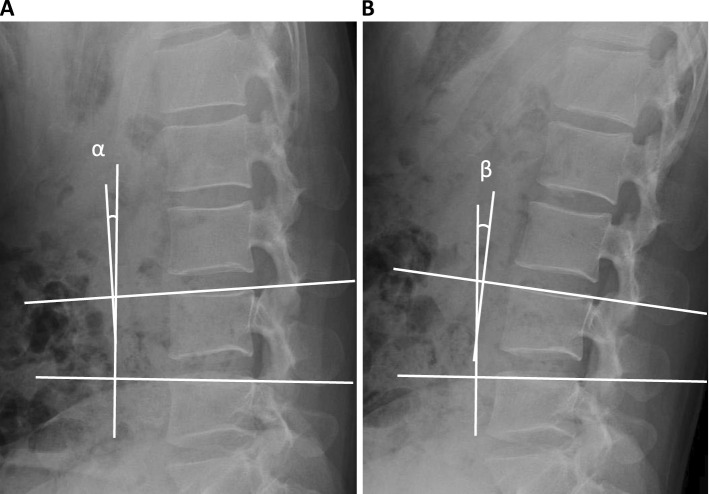

Methods: A total of 639 healthy Japanese volunteers (≥50 individuals of each decade of age from 20 to 79) without any symptom or morphological spinal abnormalities, who underwent lumbar radiograph and magnetic resonance image (MRI), were selected retrospectively. SRMs were evaluated by the flexion-extension radiographs taken in the recumbent position. Disk degenerations were assessed according to the Pfirrmann grade using MRI T2 imaging.

Results: The mean SRMs became larger in the lower lumbar level. The range of the mean SRMs was smallest at L1-2 and largest at L4-5: 6 to 9 degrees at L1/2, to peaking at 11-14 degrees at L4/5 in male, and 6-8 degrees at L1/2, to peaking at 11-17 degrees at L4/5 in female. Lumbar disk degeneration progressed faster with age in the lower lumbar spine than in the upper lumbar level. SRM did not change depending on the severity of disk degeneration in upper lumbar spine, but significantly decreased with progressive disk degeneration in the lower lumbar spine.